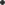

Avaskularna nekroza ( osteonekroza ) stanje koje se dešava kada cirkulacija do kostiju usporava i koštano tkivo odumire. Iako se može pojaviti na drugim kostima, ovo stanje se ipak najčešće javlja na zglobu kuka, a može biti uzrokovano frakturom kuka ili dislokacijom ( iščašenjem ) ili uslijed dugotrajne upotrebe visoke doze stereoida ( slika 7 ).

Slika 7